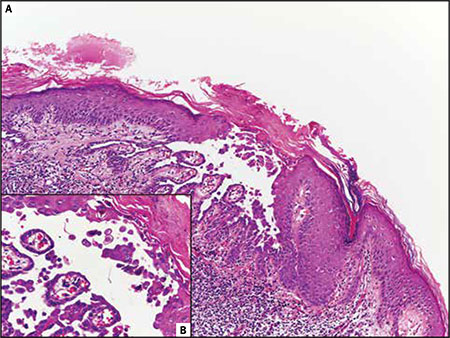

Haga usted el diagnóstico. Parte 1

Haga usted el diagnóstico. Parte 2